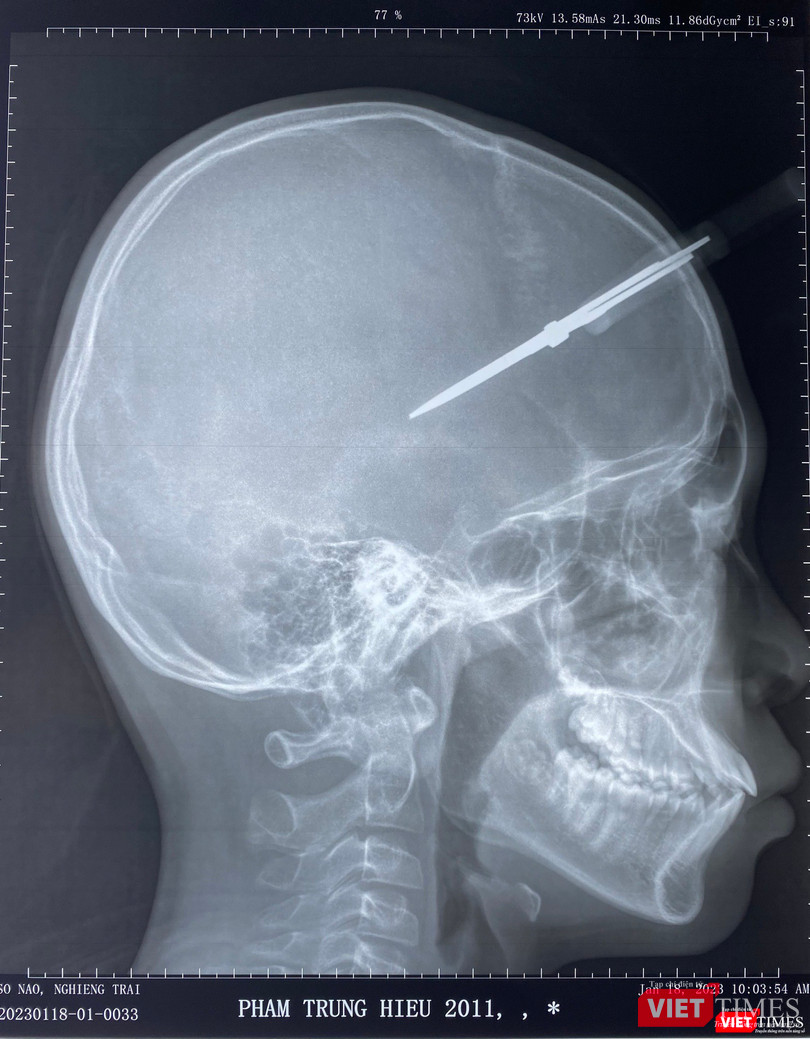

Sau khi nhanh chóng khám và cho chụp phim, các bác sĩ nhận định cây kéo nằm ở vùng thái dương, nơi có động mạch màng não giữa đi qua, rất có thể gây đứt động mạch, gây ra máu tụ ngoài màng cứng. Đặc biệt, với vị trí này, bên cạnh chiếc kéo đã gây tổn thương, còn có thể đi kèm dị vật khác như tóc của bệnh nhân, nên nếu không được xử lý sớm và triệt để, có thể gây áp xe não, viêm màng não về sau.

| Phim chụp hộp sọ bệnh nhân và chiếc kéo cắm vào thái dương |